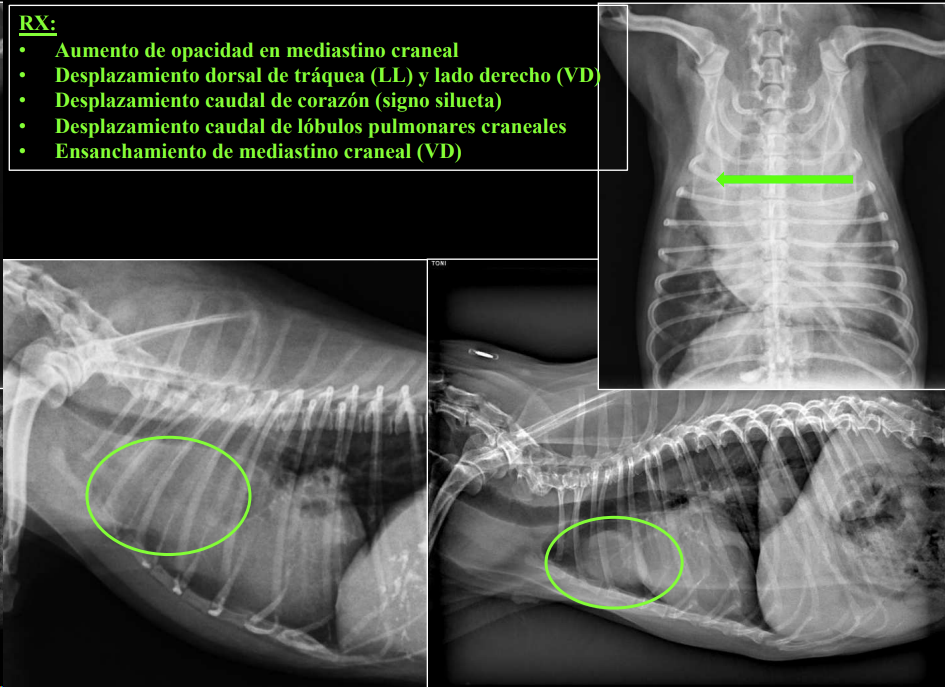

ALTERACIONES MEDIASTÍNICAS

- Alteraciones de posición del mediastino (Desplazamiento mediastino VD)

- Alteraciones en la visualización de estructuras mediastinicas (Neumomediastino LL)

- Alteraciones de la anchura del mediastino (Derrame mediastinico o masa mediastinica VD)

3. Alteraciones de anchura del mediastino craneal

- En perros: anchura < 2x VT.

- En gatos: anchura ≈ VT.

- En braquicéfalos/obesos puede verse mayor (grasa mediastínica).

- Generalmente en gatos es por un linfoma.

Causas:

- Derrame mediastínico.

- Masas mediastínicas (craneodorsales, hilares, caudodorsales, caudoventrales, craneoventrales).

- Linfomas en gato, timomas en perros.